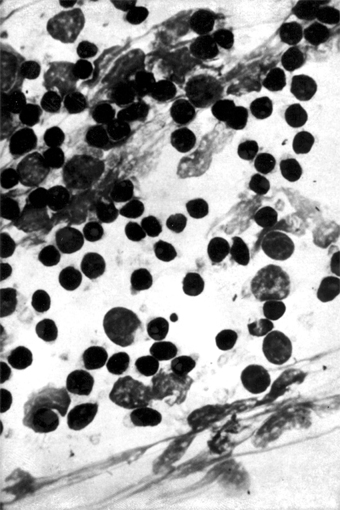

Epidemic keratoconjunctivitis is caused by adenovirus types 8, 19, 29, and 37 (subgroup D of the human adenoviruses). They can be isolated in cell culture and identified by neutralization tests. Scrapings from the conjunctiva show a primarily mononuclear inflammatory reaction (Figure 5-6); when pseudomembranes occur, neutrophils may also be prominent.

Figure 5-6

Figure 5-6: Mononuclear cell reaction in conjunctival scrapings of a patient with viral conjunctivitis caused by adenovirus type 8. (Courtesy of M Okumoto.)